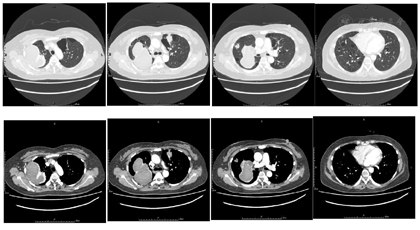

病程中间断复查胸部CT:右肺中叶切除术后,双肺多发囊性病变,右肺上叶可见一不规则结节状高密度影,并呈增大趋势,后于左肺上叶囊腔内出现新发结节状高密度影,病程中曾出现一过性右侧胸腔积液(图2)

患者后因个人原因未按上述治疗方案应用,随访患者仍有咳嗽及间断痰中带血,复查胸部CT较前无明显变化,嘱密切随诊。